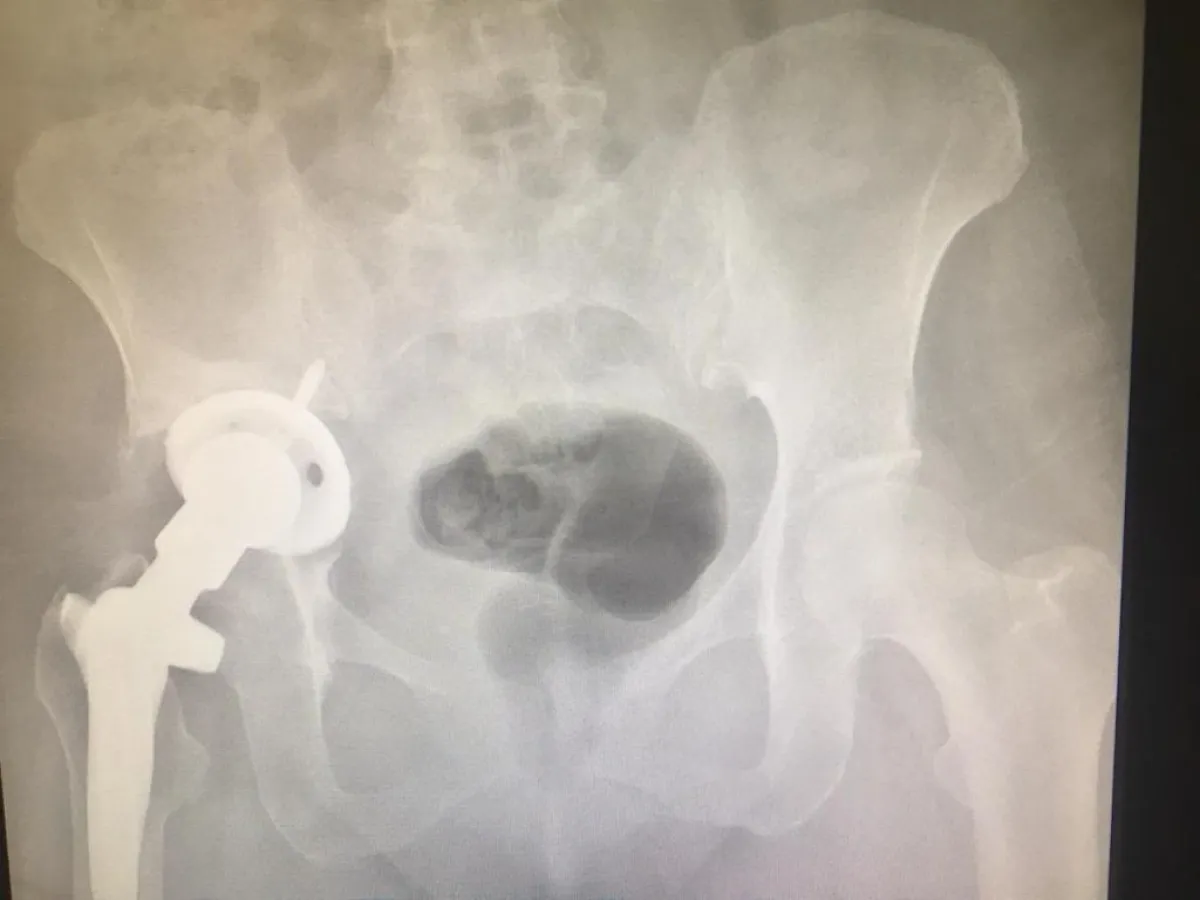

تماثلت مريضة سعودية تبلغ من العمر ٥٣ سنة بفضل من الله ، بعد نجاح أطباء واستشاريو جراحة العظام في مستشفى شرق جدة في تركيب و تثبيت مفصل الورك باستخدام الدعامات والشرائح اللازمة والتطعيم العظمي، حيث كانت المريضة تعاني من عدم القدرة على المشي ومن الآلام المستمرة في مفصل الورك الأيمن، وكانت قد أجريت لها عملية استبدال مفصل قبل ١٦ سنة ، و بعد معاينة و فحص الأطباء بمستشفى شرق جدة لحالة المريضة أظهرت الأشعة المقطعية التي أجريت لها قبل العملية وجود تخلل في المفصل القديم من جهة الورك و تحرك لمفصل الورك داخل الحوض مع تآكل في العظم ، و هذا ما دعى الأطباء إلى إجراء هذه العملية .